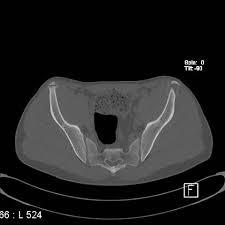

Anterior Superior Iliac Spine, Appendicular Skeleton And Joints Ppt Download : It can be palpated by putting the hands at the top of the hipbones and following the bony margins toward the front of the hips.. The posterior border of the ala, shorter than the anterior, also presents two projections separated by a notch, the posterior superior iliac spine and the posterior inferior iliac spine. Jun 28, 2021 · insertion: Asis, anterior superior iliac spine. Diagnosis is made with pelvis radiographs that shows an avulsion off the aiis. Anterior angulation of the coccyx may be a normal variant but poses a diagnostic challenge for those considering coccygeal trauma.

It provides attachment for the inguinal ligament , the sartorius muscle , 1 4 and the tensor fasciae latae muscle. The anterior superior iliac spine (asis) is the most anterior part of the iliac crest. An anterior superior iliac spine (asis) avulsion is a traumatic avulsion of the asis due to a sudden and forceful contraction of the sartorius and tensor fascia lata that occurs in young athletes. Asis, anterior superior iliac spine. This part is the most observable and palpable of the pelvis. The posterior border of the ala, shorter than the anterior, also presents two projections separated by a notch, the posterior superior iliac spine and the posterior inferior iliac spine. Diagnosis is made radiographically with displaced injuries but ct/mri may be required to diagnosis nondisplaced fractures. It provides attachment for the inguinal ligament, and the sartorius muscle. An anterior inferior iliac spine (aiis) avulsion is an apophyseal avulsion injury seen in adolescent athletes as a result of eccentric contraction of the rectus femoris. It refers to the anterior extremity of the iliac crest of the pelvis. The anterior superior iliac spine refers to the anterior extremity of the iliac crest of the pelvis. Outer lip of anterior iliac crest, anterior superior iliac spine (asis) insertion: Classification four types of coccyx have been described:

Outer lip of anterior iliac crest, anterior superior iliac spine (asis) insertion: Aug 29, 2017 · aiis, anterior inferior iliac spine; Asis, anterior superior iliac spine. The posterior border of the ala, shorter than the anterior, also presents two projections separated by a notch, the posterior superior iliac spine and the posterior inferior iliac spine. An anterior superior iliac spine (asis) avulsion is a traumatic avulsion of the asis due to a sudden and forceful contraction of the sartorius and tensor fascia lata that occurs in young athletes. The tensor fasciae latae and sartorius muscles of the thigh have their origins at the anterior superior spine. An anterior inferior iliac spine (aiis) avulsion is an apophyseal avulsion injury seen in adolescent athletes as a result of eccentric contraction of the rectus femoris. It provides attachment for the inguinal ligament, and the sartorius muscle. The posterior superior iliac spine serves for the attachment of the oblique portion of the posterior sacroiliac ligaments and the multifidus. It provides attachment for the inguinal ligament , the sartorius muscle , 1 4 and the tensor fasciae latae muscle. It can be palpated by putting the hands at the top of the hipbones and following the bony margins toward the front of the hips. Classification four types of coccyx have been described: Diagnosis is made radiographically with displaced injuries but ct/mri may be required to diagnosis nondisplaced fractures.